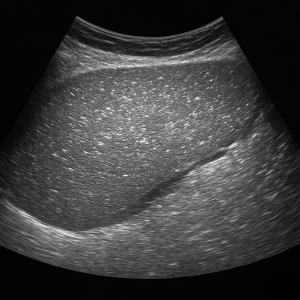

간

간은 복부초음파에서 가장 먼저 살펴보는 장기예요. 초음파로 지방간, 간경변, 결절, 낭종, 혈관종, 간암 등 여러 가지 변화를 감지할 수 있고, 간 기능 검사에 이상이 있을 때 특히 중요하게 확인해요.

간 질환

- 지방간

간에 기름이 쌓이면 초음파에서 밝고 반짝이는 모습으로 보일 수 있어요. 요즘 지방간이 흔한데, 초음파로 쉽게 확인되서 유용합니다. - 간경변